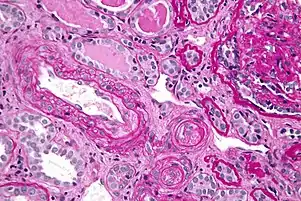

Kidney involvement, in scleroderma, is considered a poor prognostic factor and frequently a cause of death.[13]

The most important clinical complication of scleroderma involving the kidney is scleroderma renal crisis (SRC), the symptoms of which are malignant hypertension (high blood pressure with evidence of acute organ damage), hyperreninemia (high renin levels), azotemia (kidney failure with accumulation of waste products in the blood), and microangiopathic hemolytic anemia (destruction of red blood cells).[14] Apart from the high blood pressure, hematuria (blood in the urine) and proteinuria (protein loss in the urine) may be indicative of SRC.[15]

In the past, SRC was almost uniformly fatal.[16] While outcomes have improved significantly with the use of ACE inhibitors,[17][18] the prognosis is often guarded, as a significant number of patients are refractory to treatment and develop kidney failure. About 7–9% of all diffuse cutaneous scleroderma patients develop renal crisis at some point in the course of their disease.[19][20] Patients who have rapid skin involvement have the highest risk of renal complications.[21] It is most common in diffuse cutaneous scleroderma, and is often associated with antibodies against RNA polymerase (in 59% of cases). Many proceed to dialysis, although this can be stopped within three years in about a third of cases. Higher age and (paradoxically) a lower blood pressure at presentation make dialysis more likely to be needed.[22]

Scleroderma renal crisis (SRC) is a life-threatening complication of systemic sclerosis that may be the initial manifestation of the disease. Renal vascular injury (due in part to collagen deposition) leads to renal ischemia, which results in activation of the renin-angiotensin-aldosterone system (RAAS). This raises blood pressure and further damages the renal vasculature, causing a vicious cycle of worsening hypertension and renal dysfunction (e.g., elevated creatinine, edema). Hypertensive emergency with end-organ dysfunction (e.g., encephalopathy, retinal hemorrhage) is common. Thrombocytopenia and microangiopathic hemolytic anemia can be seen. Urinalysis is usually normal but may show mild proteinuria, as in this patient; casts are unexpected.